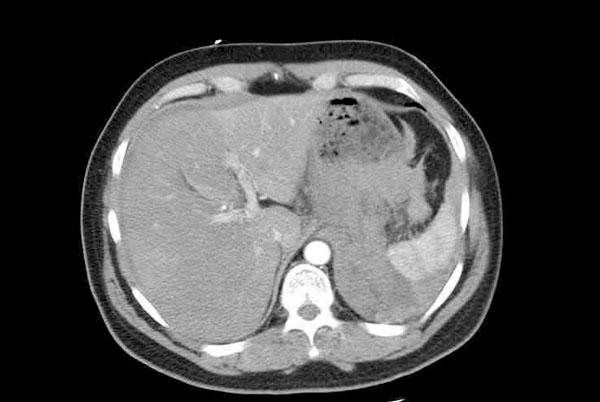

Splenic artery aneurysms are rare. We discuss a case of a 58-year-old gentleman presenting with collapse and shock secondary to spontaneous splenic artery aneurysm rupture. Patient underwent laparotomy and splenectomy then discharged home within a week of presentation.

脾动脉瘤很少见。我们讨论一例58岁男性患者,因自发性脾动脉瘤破裂出现虚脱和休克。患者接受了剖腹手术和脾切除术,在就诊后一周内出院回家。